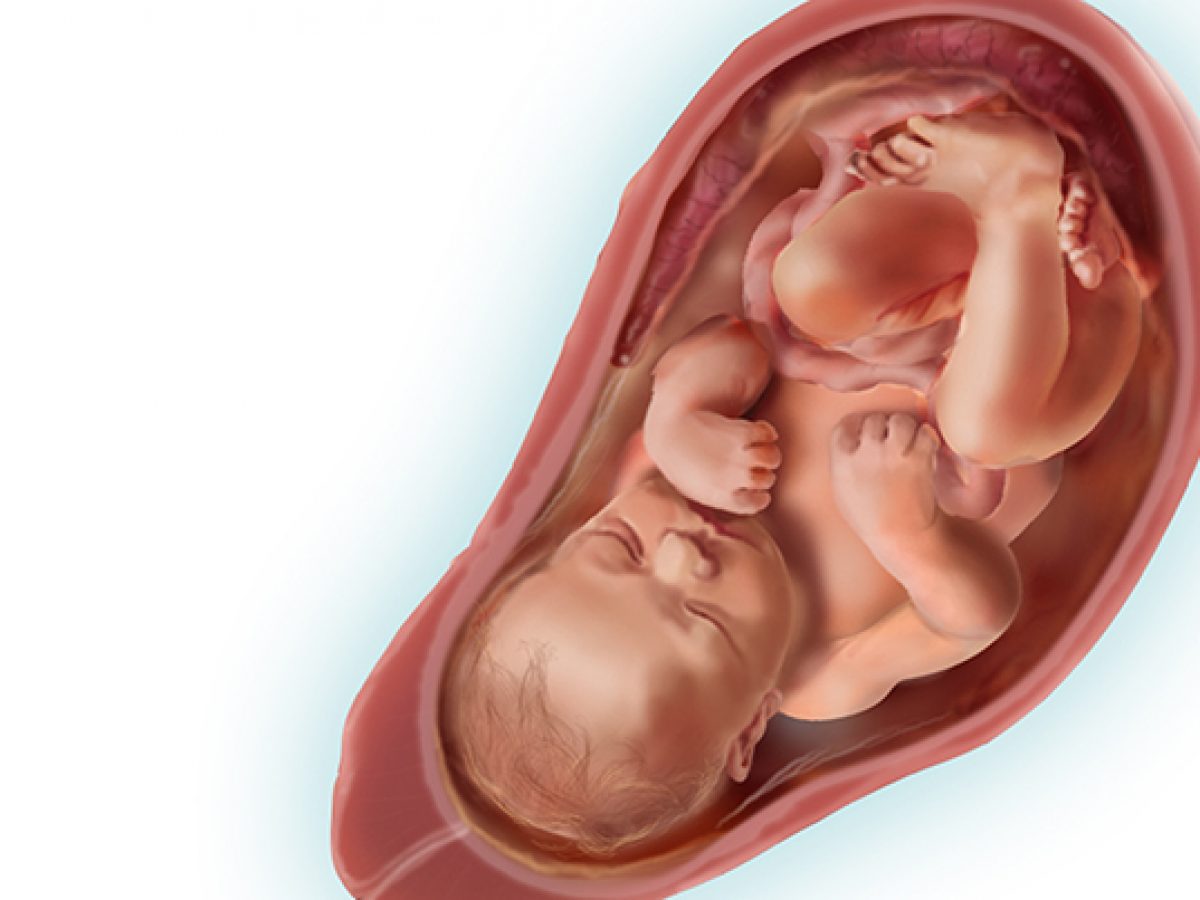

Плод 39 Недель Фото

Плод 39 Недель Фото 100 фото